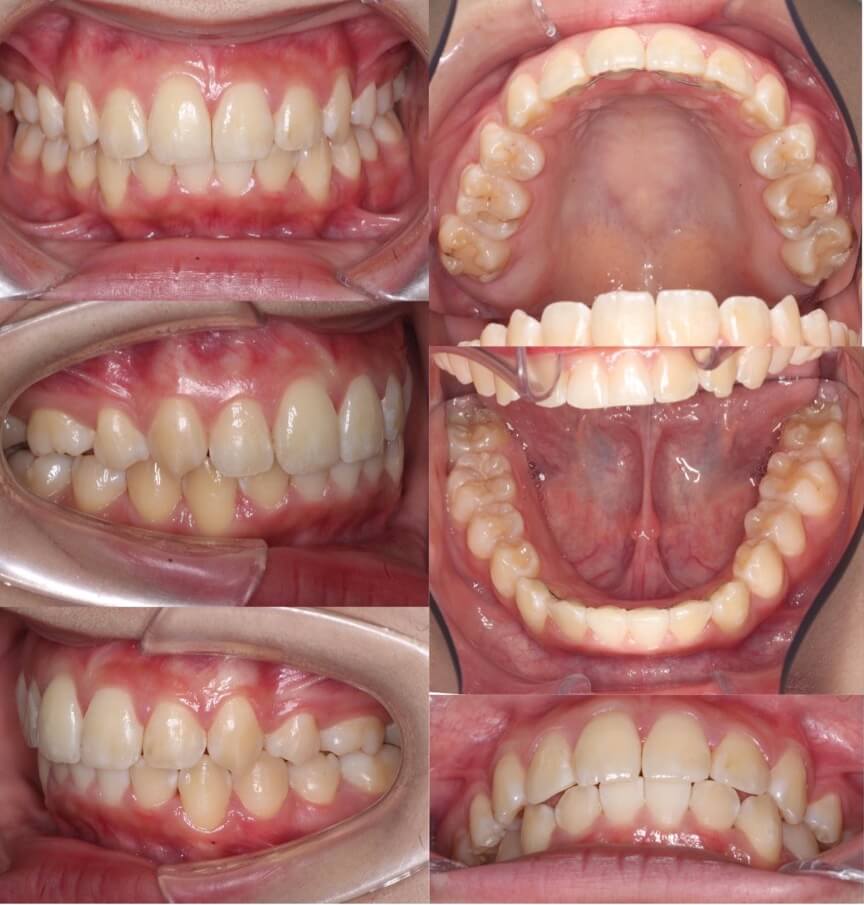

高校生女性・唇側矯正装置・上抜歯

上の前歯が前に出ているため下唇に当たり口が閉じづらいという症状を、抜歯を併用して前歯を引っ込めて治しました。術後は奥歯を含めて理想的なかみ合わせになり、スマイルも大きく変化しました。ご本人からも大変満足していただけました。少し前歯が小さめですが、唇側矯正装置であればしっかりと歯の動きをコントロールする事ができます。

<症例概要> 難易度★★★☆☆

主訴:出っ歯

年齢・性別:高校生女性

住まい:千葉県船橋市

症状:上顎前突・叢生・過蓋咬合・右側シザースバイト

治療方針:上抜歯空隙閉鎖(中等度固定)・ストリッピング

治療装置:唇側矯正装置

固定装置:ナンスホールディングアーチ

抜歯:上第一小臼歯(計2本)

治療期間:2年2か月

リテーナー:上プレートタイプ+クリアタイプ・下フィックスタイプ

治療費用:968,000(税込)

代表的副作用:痛み・治療後の後戻り・歯根吸収・歯髄壊死・歯肉退縮